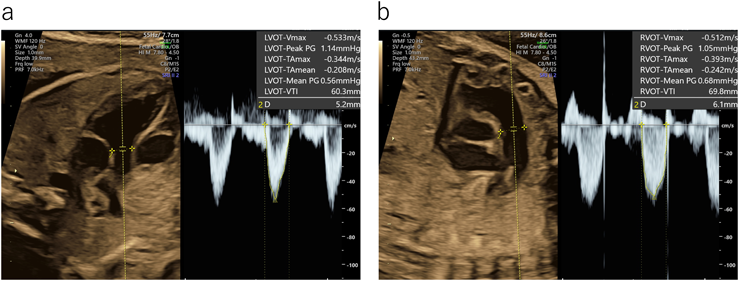

10. 総心拍出量(combined cardiac output: CCO)

CCOは左右心室の心拍出量の合計である.体重当りで評価され,正常では週数によらず425~465 mL/min/kg程とされる7, 8).各心室の拍出量(CO)は,半月弁の弁輪部(大動脈弁と肺動脈弁)の断面積,同部位のドプラ波形をトレースしたvelocity time integral(VTI),心拍数の積をもって算出する.CO(mL/min)=半月弁輪径(cm)2/4×3.14×VTI(cm)×HR(/min)(ドプラ入射角度<20°)で求める(Fig. 13).正常では右室拍出量は左室の約1.4倍とされ,右室優位である7, 8).半月弁の弁輪径,ドプラの入射角度,サンプルゲートの位置などの少しの違いによりCOの値は大きく変わるため胎児では使いにくい面がある. CO( mL / min ) 半月弁輪径 (cm) 2 4 ×3.14×VTI(cm)×HR(/min) CCO( mL / min / kg ) 右心室CO左心室CO 推定体重(kg)

Pediatric Cardiology and Cardiac Surgery 40(4): 250-259 (2024)

Fig. 13 総心拍出量(combined cardiac output; CCO)

a:左心室CO (0.522/4)×3.14×6.03×133(心拍数)=170 mL/min.b:右心室CO (0.612/4)×3.14×6.98×133=271 mL/min.CCO:170+271=441 mL/min推定体重は0.956 kgであり体重当りのCCOは461 mL/min/kg.